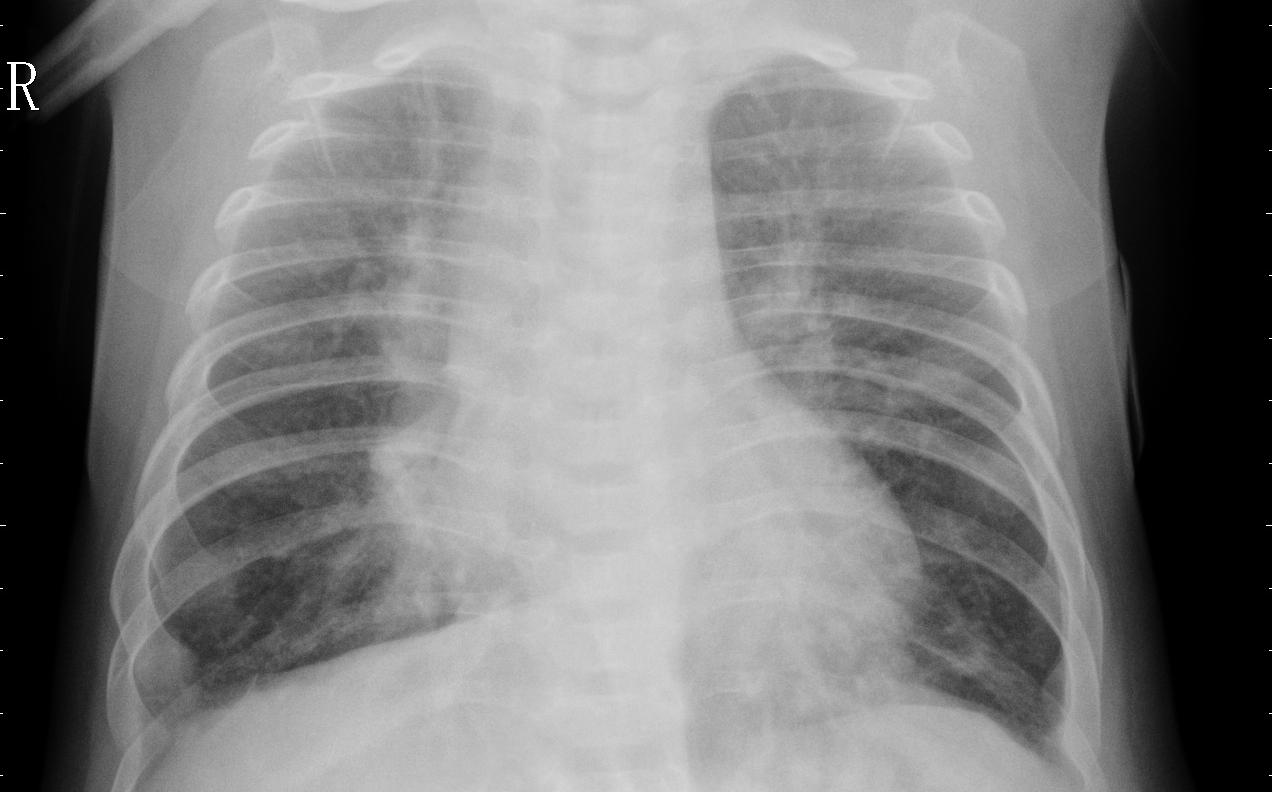

We conduct human subject experiments on two image classification datasets: a natural image dataset, Butterflies v.s. Moths (BM) and a medical image dataset of chest X-rays (CXR). For BM, we followed Singla et al. (2014) and acquired 200 images from ImageNet Krizhevsky et al. (2012). BM is a binary classification problem and each class contains two species. CXR is a balanced binary classification subset taken from Kermany et al. (2018) with 3,166 chest X-ray images that are labeled with either normal or pneumonia. We randomly split the datasets following 60%:20%:20% ratio. The classification accuracy with our base supervised learning models are 97.5% for BM and 97.3% for CXR. We only present results with human subjects in the main paper, but results from simulation experiments with TML as a synthetic agent, such as filtering triplets providing better results, are qualitatively consistent. See §D and §E in the appendix for more details.

5.3 Results on Chest X-rays

We use the same experimental setup as BM to evaluate HC and MLE representations in CXR.

H2H comparison results show HC NI examples are slightly preferred over MLE NI examples but the difference is not statistically significant. We recruit 50 Prolific workers to each make 20 H2H comparisons between HC NI examples and MLE NI examples. The mean preference for HC over MLE is 0.516 with a 95% confidence interval of ±0.0725plus-or-minus0.0725\pm 0.0725 (p=0.379𝑝0.379p=0.379 with one-sample t-test). H2H comparison in CXR is especially challenging as laypeople need to differentiate between two chest X-rays in the same class, hence the slightly worse performance in H2H compared to BM.

Similar to BM, HC outperforms MLE in both neutral and persuasive decision support in CXR. As expected, Fig. 4(b) shows that pneumonia classification is a much harder task than butterfly vs. moth classification, indicated by the lower accuracies across all conditions. In neutral decision support, HC enables much better accuracy than MLE (79.1% vs. 63.8%, p=2e8𝑝2e8p=2\mathrm{e}{-8} with two-sample t-test). In fact, similar to the BM setting, MLE provides similar performance with RIRO (63.8% vs. 65.9%, p=0.390𝑝0.390p=0.390), suggesting that MLE representations are no different from random representations for selecting nearest neighbors within a class. To contextualize our results, we would like to highlight that our crowdworkers are laypeople and have no medical training. It is thus impressive that human-compatible representations enable an accuracy of almost 80% in neutral decision support, which demonstrates the potential of human-compatible representations.

In persuasive decision support, HC provides the highest decision support accuracy at 90.0%, also much higher than MLE at 77.0% (p=2e10𝑝2e10p=2\mathrm{e}{-10}). Again, while we do not recommend persuasive decision support as a policy for decision support in practice, these results show that our human-compatible representations are indeed more compatible with humans than MLE representations.